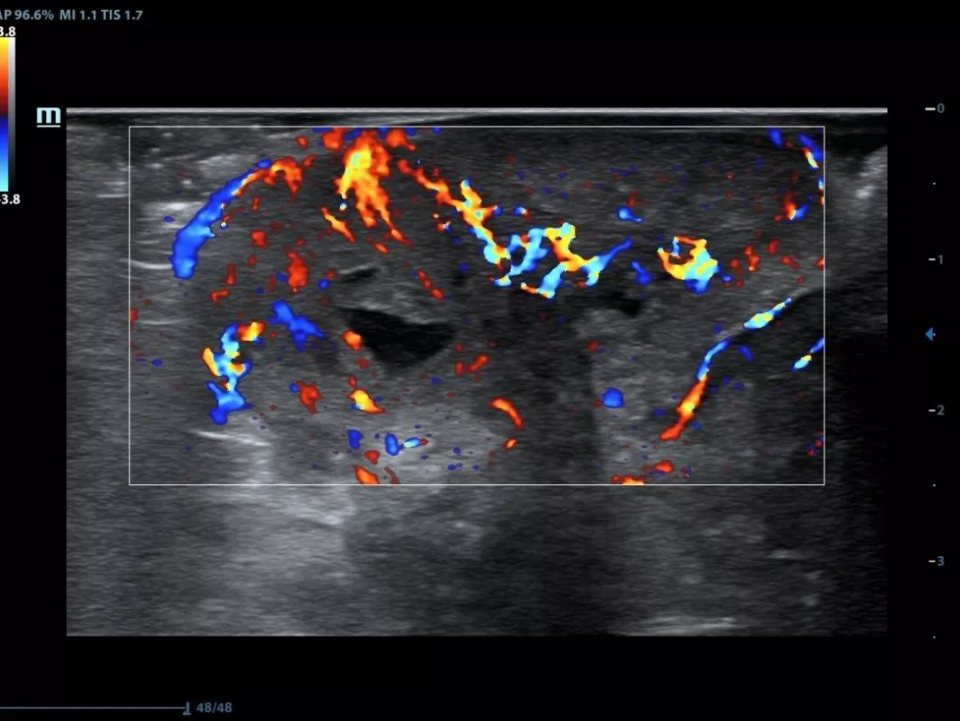

HR flow of breast tumor

ComboWave Transducer Technology

X-Insight provides ComboWave linear transducers for thyroid, breast, vascular and other applications. The transducers utilize a new type of composite piezoelectric material to dramatically optimize the acoustic spectrum and reduce acoustic impedance, allowing clinical experts to experience outstanding performance with extreme image resolution and uniformity.